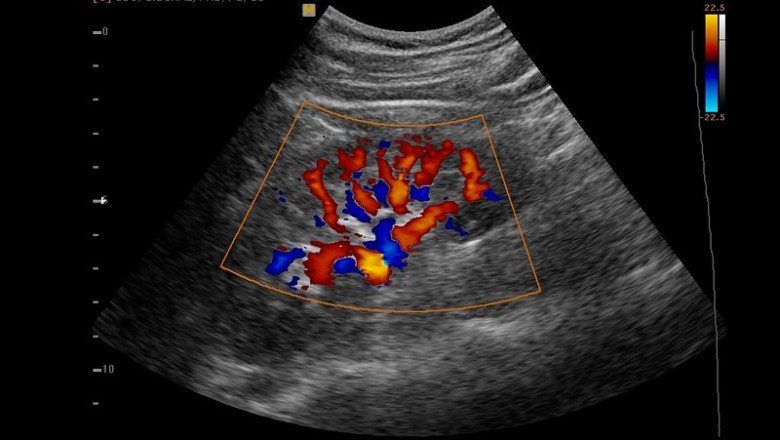

A Doppler Ultrasound is a test that measures the quantity of blood flow through your arteries and veins, often those that provide blood to your arms and legs. It uses high-frequency sound waves. Blood flow tests, sometimes referred to as vascular flow studies, are able to identify aberrant blood flow within an artery or blood vessel. Blood clots and impaired circulation are just two diseases that can be diagnosed and treated with this. A blood flow study may involve the use of a Doppler ultrasonography.

A Doppler Ultrasound is a quick, painless, and minimally invasive technique. The test gives your doctor crucial knowledge about the blood flow through your principal arteries and veins. Also, it can show places in the arteries that have restricted blood flow or are obstructed, which could eventually result in a stroke.